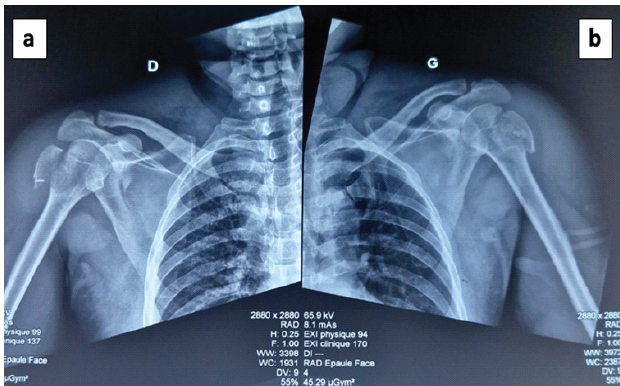

It was a 52-year-old patient, with no known medical history, admitted to the emergency department for bilateral closed shoulder trauma following a tonic-clonic seizure at 4 h after the trauma. On admission, the patient had a blood pressure of 160/100 mm Hg and a clear consciousness. Symmetrical and bilateral clinical examination of the shoulders revealed the signs of bilateral anterior dislocation of the shoulders with an external axe blow and irreducible abduction (Fig. 1a). Sensitivity and motor skills in the axillary nerve area were preserved. Peripheral pulses were present. The examination of the other devices was normal. After conditioning the patient by taking a venous line, administering analgesics and temporarily immobilizing the patient, an imaging and biological assessment was requested. Standard shoulder X-ray revealed bilateral dislocation in its anterior subcoracoid variety associated with fracture of the major tubercles (Fig. 1b, c, d, e).

Figure 1: Clinical appearance and X-rays showed the shoulders dislocations. (a) Clinical appearance of the shoulders showed signs of bilateral anterior dislocation of the shoulders with an external axis blow and irreducible abduction (b and c). Right Shoulder’s X-rays showed the shoulder dislocation with major tubercle fracture (d and e). Left Shoulder’s X-rays showed the shoulder dislocation with major tubercle fracture.